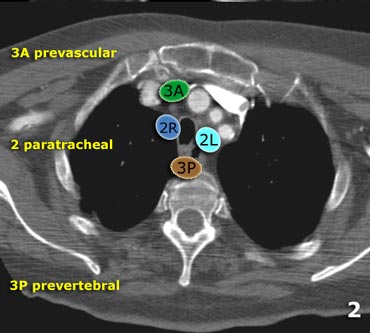

Hilar Lymph Nodes Map

mavink.com

mavink.com

Hilar Lymph Nodes Map

mavink.com

mavink.com